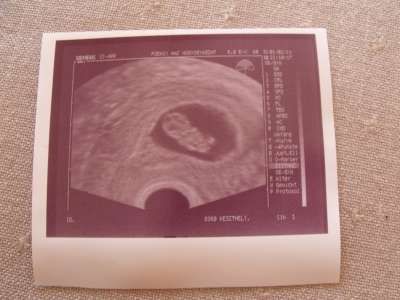

jelentem, az én időpontomat i s lhet módosítani ma vagyunk 8+5 naposak szeptember 10-re vagyok most kiirva!!most 2,09 cm..pöttömke. éshallottam dobogni végre a szivét!!!

igaz h rövid ideig de hallottam. kicsi párom meg kint hallotta az ajtó előtt de utána bejött, pár szót váltotunk a dokival, és 4 hét mulva kell visszamennem. addig semmilyen vizsgálatra nem küldött, azt modnta innentől mindent ő intéz..(lehet h vért vesz vagy laborbeutalóra gondolt????????)sebaj, négy hétig igy még vizsgálatok tekintetében nyugi van..Komolyan mondom az egyik legszebb pillanat mikor először halljuk dobogni a picikénk szivét..legalábbis nekem biztosan.. és milyen megnyugtató..most jól érzem magam..(leszámitva h leszakad a derekam..)

A következő uh már hasi lesz arra már biztosan a párommal megyek be..